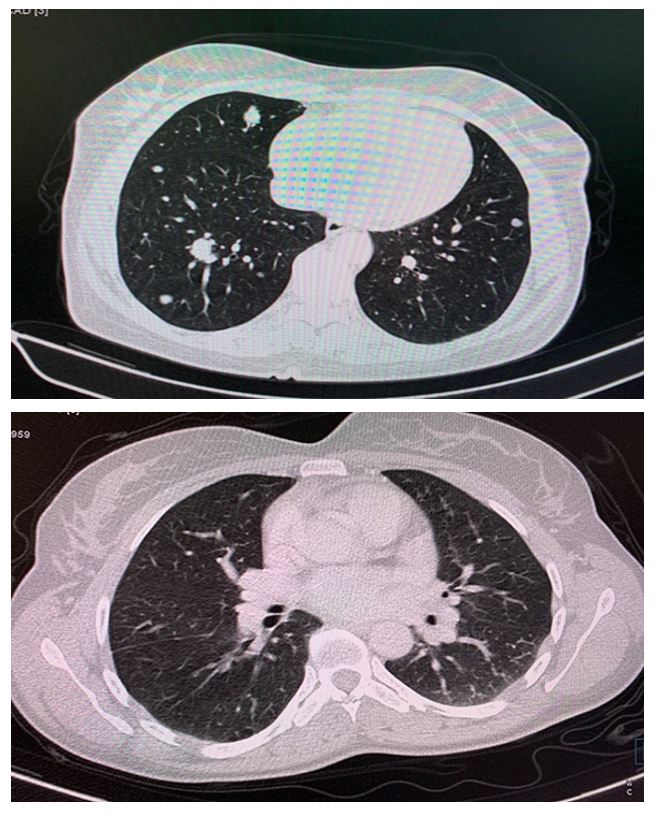

Open AccessClinical Case

Primary Lung Cancer Versus Metastasis of Thyroid Cancer the Utility of FDG PET CT

Sánchez-Ríos Carla Paola, Guzmán-Casta Jordi, Riera-Sala Rodrigo Fernando, López-Vratny Claudia, Hernández-Dehesa Itzel Ariadna, González-Araujo Andrea, Correa-Cano Rafael, Peña-Mirabal Erika, Aguirre-Pérez Natalia, Ayala-Domínguez Adriana, Elvira-Fabián Karina, Carrasco-Cara Chards Sonia, Martínez-Barrera Luis Manuel, Rodríguez-Cid Jerónimo Rafael, Alatorre-Alexander Jorge Arturo

International Journal of Innovative Research in Medical Science·December 12, 2020